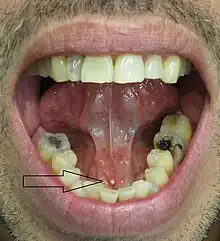

The stone seen in the submandibular duct on the person's right side